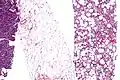

Histopathology of liposarcomas

Fig. 1 Micrograph of bone formation in a liposarcoma tumor

Fig. 2 Micrograph of a dedifferentiated liposarcoma tumor

Fig. 3 Lower-power micrograph of myxoid liposarcoma tumor- Fig. 4 Higher-power micrograph of myxoid liposarcoma tumor

Histopathologically, ALT/WDL tumors are divided into adipocytic/lipoma-like, sclerosing, and inflammatory variants with adipocyte/lipoma-like being the most common. Adipocytic/lipoma-like ALT/WDL tumors consist of lobules of mature fat cells variably intersected with irregular fibrous septa (see the adjacent H&E stained photomicrograph). Sclerosing ALT/WDL tumors, the second most common variant, develop primarily in the retroperitoneal and paratesticular areas; it consists of scattered, atypical stromal cells within a collagenous (i.e. collagen-containing) stromal tissue background. Rare vacuole-containing lipoblasts populate this tissue. Inflammatory ALT/WDL tumors are the rarest variant. they occur most frequently in the retroperitoneum and consists of chronic inflammatory cells, e.g. lymphocytes and plasma cells plus occasional lymph node-like follicles interspersed throughout a tissue background containing fat cells.[14]

The histopathological appearance of DDL tumors (see Fig. 2 in the below Histopathology of liposarcomas section) varies widely but most frequently exhibits features of undifferentiated pleomorphic sarcomas (which are tumors densely populated with variably sized and shaped cells containing variability sized and shaped nuclei) or spindle cell sarcomas (which are tumors consisting of spindle-shaped cells in a connective tissue background). Different parts of DDL tumors often show variations in the appearances of their background connective tissues: these tissues may be myxoid (i.e. consisting of a clear, mucus-like substance which when stained using a standard H&E stain method appears more blue or purple than the red color of normal tissues) or myxocollagenous (i.e. high collagen fiber content in a myxoid background), and, in ~5% of cases, have areas of osteoid (see Fig. 1 in the below Histopathology of liposarcomas section) or cartilaginous material. The tumors also show large variations in their cell contents. For example, up to 10% of DDL tumors have areas with ALT/WDL histopathology [8] and rare cases of DDL have areas containing meningothelial-like whorls of flat cells.[24][25]